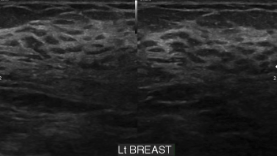

Normal breast US appearance

• Tissue

• Premammary zone (hypoechoic)

• Mammary zone (hyperechoic)

• Retromammary zone (hypoechoic)

• Pectoralis major (hyperechoic)

• Cooper’s ligament (hyperechoic bands)